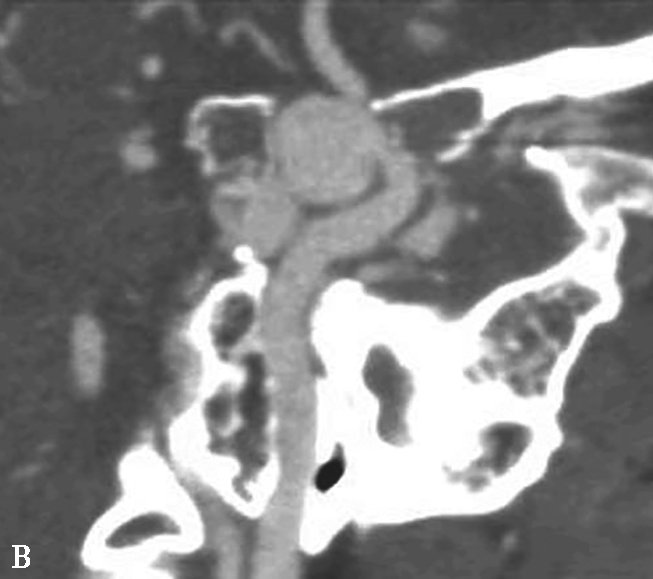

图1-2-6 左侧颈内动脉创伤后假性动脉瘤突入蝶窦

患者男,36岁,车祸伤后左侧额部硬膜外血肿清除并颅骨去骨瓣减压术后半年,间断大量鼻出血半个月就诊。A.颅脑CTA检查MPR横断面重组,可见蝶窦内软组织密度影,部分与颈内动脉同步均匀强化,并通过蝶窦骨质缺损与海绵窦游离段颈内动脉内侧壁相连,蝶窦内病变前缘部分未见强化;B.CPR(曲面重组)重建,示假性动脉瘤瘤体与邻近颈内动脉以宽基底相连,骨折断端与颈内动脉壁关系密切;C.CTA VR重建,示瘤体与左侧颈内动脉海绵窦段相连;D.左侧颈内动脉DSA检查可见海绵窦段假性动脉瘤显影,因瘤体盗血致其远端分支显影不满意